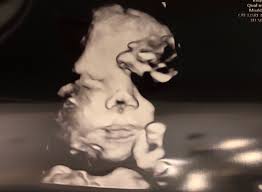

If the 2D ultrasound does not demonstrate two nasal bones then 3D ultasound may be useful. An ultrasound scan There is no risk to the baby from either of these procedures. October 15 2018 Shane Dale According to the National Down Syndrome Society NDSS during the normal fertilization of a womans egg by a mans sperm the resulting nucleus of each cell in a fetus contains 23 pairs of chromosomes half of which are inherited from each parent.

For this reason 3D ultrasound reconstruction of the nasal bone and other facial bones is useful. At this stage the babys legs arms fingers and toes should be fully formed. Mothers should not be encouraged to have an ultrasound called a.

Of the many defects 3D 4D ultrasound has been useful in evaluating the skeletal and cardiovascular systems in fetuses with this condition. But keeping tabs on your babys growth can be a good thing and knowledge is power. By combining the results of the two parts of the test it is possible to identify if a pregnant woman is at increased risk of having a baby with Down syndrome.